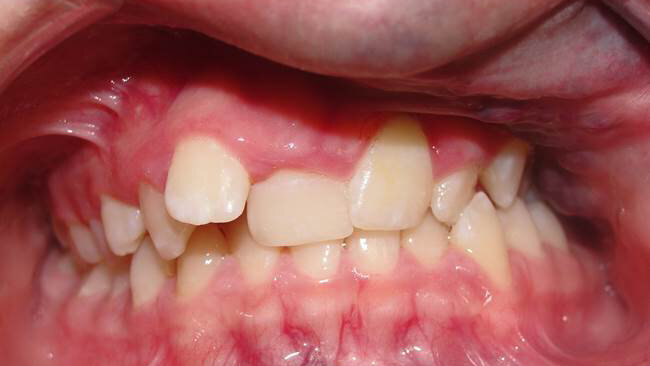

Hemifacial microsomia results from the malformation of the 1st and 2nd branchial arches. Involves mostly unilateral condylar underdevelopment, it may be associated with variable abnormalities of the external and middle ear, has similar manifestations with Goldenhar syndrome, and its etiology is heterogeneous. The extent of TMJ involvement primarily determines severity, prognosis, timing and type of treatment. Face asymmetry in hemifacial microsomia is characterized by chin deviation. Occlusal manifestations include lower dental midline deviation, unilateral cross bite, tilting of the occlusal plane, all of them towards the affected side (Figure 2). Apart from ear abnormalities, soft tissue defects may include skin tags, facial clefts, cranial nerve function, soft palate function, bulk of subcutaneous soft tissue, muscles of mastication and facial expression, macrostomia, and skin tags (3).

Figure 2. Facial photograph of a 13-year-old girl with hemifacial microsomia (right side) (a). The discrepancies include asymmetries in the mandibular body, ramus, and condyle, as well as involvement of the ear. Malocclusion is characterized by right posterior crossbite, tilting of the occlusal plane and lower dental midline deviation to the affected side (b).